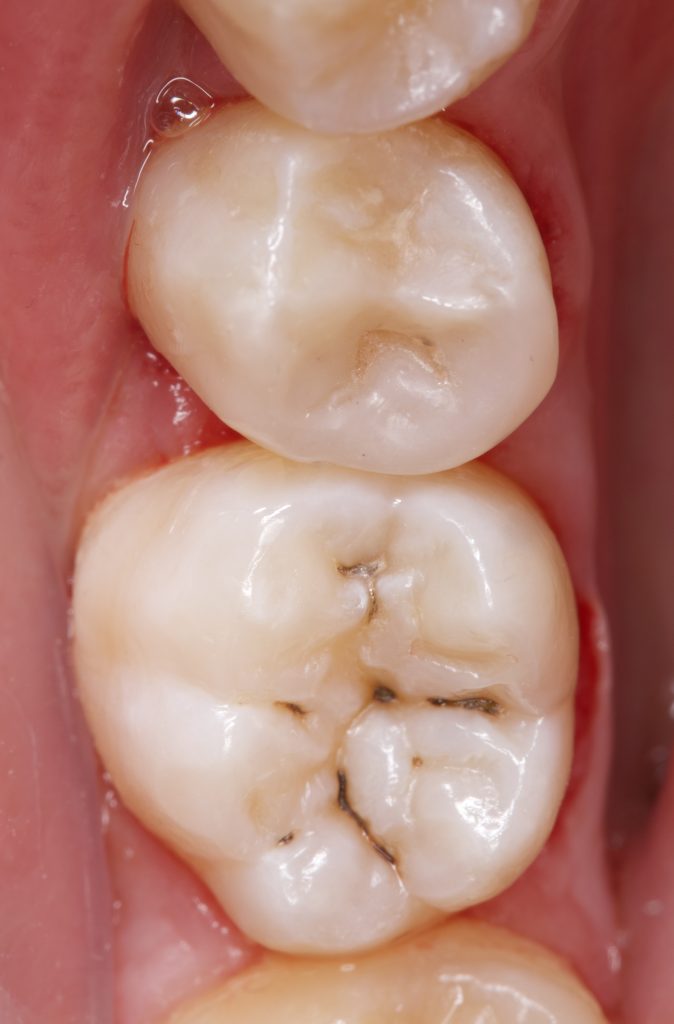

Restoring posterior teeth with extensive proximal lesions requires a precise combination of adhesive protocols, anatomical reproduction, and mechanical reinforcement. This case report describes a Class II direct composite restoration using fiber-reinforced dentin replacement, sandblasting for enhanced adhesion, a dual-flowable approach for adaptation, and the Functional Matrix Technique (FMT) for anatomical accuracy.

A patient presented with secondary caries under a defective restoration in the maxillary second premolar. The decay extended subgingivally, requiring deep margin management. Rubber dam isolation was applied to ensure a moisture-free environment and protect adjacent tissues during preparation.

Step 7 – Incremental Layering with Nanofilled Composite

- A nanofilled universal composite (3M) was placed incrementally, each cusp sculpted separately and light-cured for 20 seconds.

Step 8 – Finishing and Polishing

- Occlusion was checked in static and dynamic movements.

- Final polishing was achieved with a multi-step polishing kit, restoring enamel gloss and smooth margins.